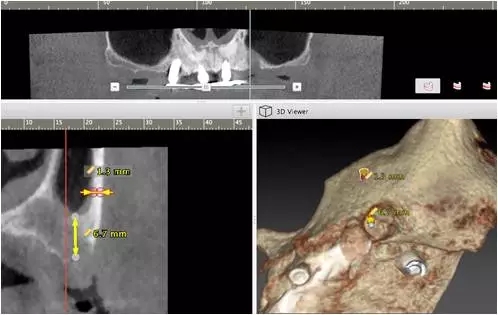

10個月后出現(xiàn)左上頜咬合痛,X線檢查發(fā)現(xiàn)上頜左側(cè)前磨牙區(qū)傾斜種植體周圍低密度影,臨床檢查種植體松動,其余種植體骨結(jié)合良好,遂拔除該種植體(圖3-4)。愈合3個月,CBCT片顯示:25區(qū)種植窩空虛(圖5),愈合不佳,26區(qū)竇底剩余骨高度不足2mm(圖6),其余種植體骨愈合良好,15區(qū)傾斜種植體邊緣骨疑似吸收至第三螺紋(結(jié)合全景片)?;颊咭蠊潭ㄐ迯?fù)。

圖5

圖6

2、增加上頜種植體數(shù)量,分別與16、25、26植入3顆,行6顆種植體支撐的常規(guī)種植固定義齒修復(fù)(圖7)。16、25、26區(qū)剩余骨高度嚴(yán)重不足是該方案的不利方面,存在因需要上頜竇底提升手術(shù)所帶來的相應(yīng)手術(shù)風(fēng)險。但是,上頜竇底提升術(shù)是一個成熟、可靠的技術(shù)方法,經(jīng)過與患者充分溝通,最終選擇了這一方案。

圖7